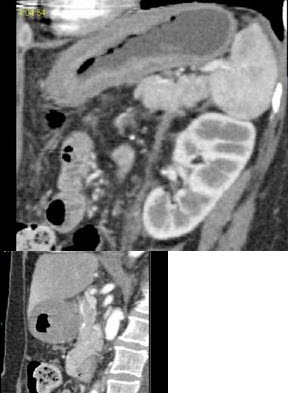

根据所提供的图像,最可能的诊断是( )

A:鹿角状结石

B:肾盂积水

C:肾动静脉畸形

D:黄色肉芽肿性肾盂肾炎

E:肾盂旁囊肿